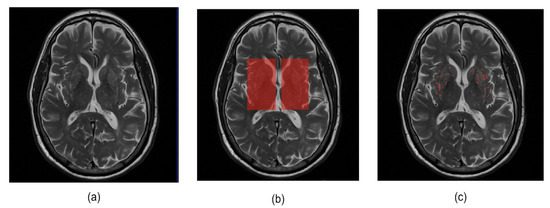

In this study, we conducted experiments using a dataset of 456 images from 76 participants. The basal ganglia ROI mask is used to acquire six 2D images from T2-weighted MRI and ePVS segmentation masks corresponding to the basal ganglia regions. These images were then employed in a deep learning model for the enhancement of ePVSs. Table 2 shows the characteristics of the ePVS rating score distribution for a total of 456 images extracted from the basal ganglia area. In addition, the images obtained by adding the ePVS segmentation mask (0, 1) to each 2D image (0–1 range) are used as the output for the deep learning model for enhancement of ePVS. Figure 4 provides examples of T2-weighted MRI, basal ganglia ROI, and ePVS ROI images that we used in our study.

Figure 4.

Illustration of example data used in this study. (a) Original T2-weighted MRI, (b) basal ganglia ROI mask, and (c) ePVS segmentation mask.